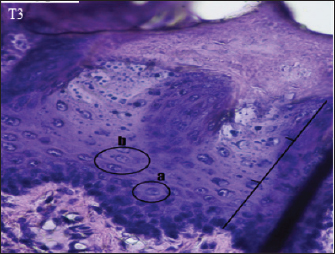

Fig. 5. Histopathological appearance of the rat tongue epithelium in group T3, microscope at ×400. (a) irregular polygonal cell shape in the spinosum layer; (b) oval cell shape in the granulosum layer.

The histopathological appearance of the rat tongue epithelium in the T3 group was close to that of normal epithelium. It is characterized by regular stratification cells. Variations in the shape and size of the nucleus are slight. Hyperchromatic nuclei are found in the basal and parabasal layers. Irregular polygonal cell shapes in the spinosum layer and oval cell shapes in the granulosum layer were also seen in this group (Fig. 5).

In several visual fields, cells in the T3 group had decreased dysplasia, and their condition was similar to that of the negative control group. This suggests that C. cinerariifolium leaf extract at a concentration of 200 mg/kg bw can effectively lower the degree of dysplasia in the oral epithelium. Differences in the terpenoid and flavonoid content of extract and the degree of dysplasia between the treatment groups were reasonably considerable. Other studies have shown that terpineol component in the extract has an anticancer effect by inhibiting the signaling of the transcription factor NF-kB in tumor cells, hence decreasing gene expression in malignancies (Hassan et al., 2010). Terpenoids also function as anticancer agents in human oral cancer cell lines by inducing cell cycle arrest and death in OSCC cells via caspase cascade (Kim et al., 2022). In the extract of C. cinerariifolium leaf, there is also the flavonoid kaempferitin, which can boost the production of the p53 oncogene protein, hence promoting an increase in apoptosis (Siddiqui et al., 2020). The process of inhibiting the production of oncogene proteins and enhancing the expression of tumor suppressor genes can stop aberrant cell proliferation and lower the severity of dysplasia. According to Mutiah et al. (2020), 96% ethanolic extract of C. cinerariifolium (Trev.) leaf based on in silico analysis contains glutamic acid in hydrogen bonds, which inhibits tumor development by blocking angiogenesis.